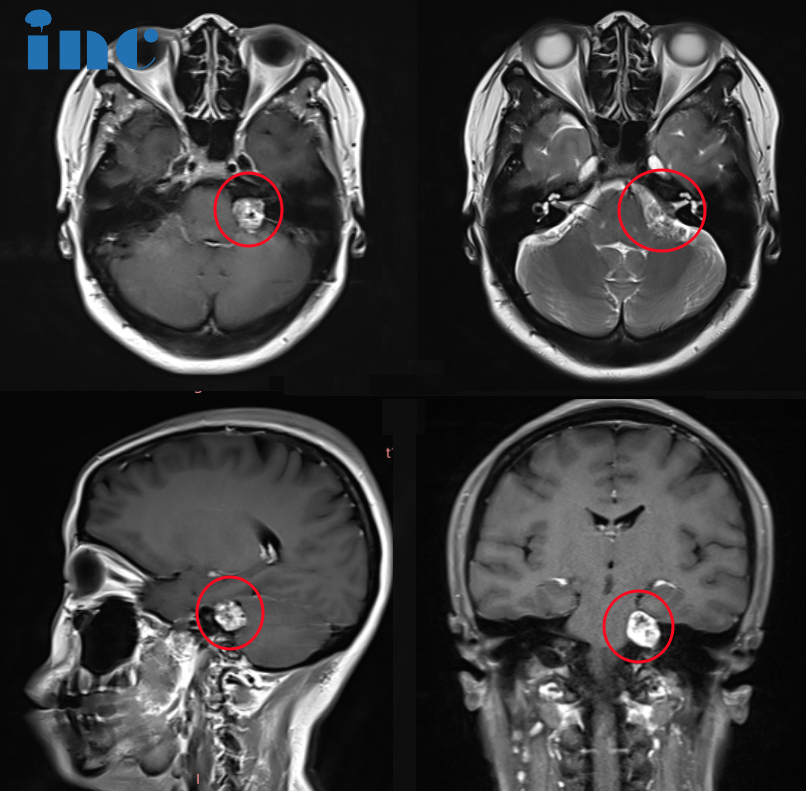

03、延髓占位性病变手术风险较大,只能保守治疗吗?

病史摘要:15岁男孩浩宇一家也有着吴女士类似的焦虑。浩宇2023年3月中旬以来持续头痛、嗜睡等症状。行颅脑磁共振平扫和增强检查,提示延髓背侧偏左、左侧小脑扁桃体前见结节样异常信号,怀疑胶质瘤。但医生表示头痛症状和延髓占位病变关系不大。有的医生建议手术治疗,但手术风险高,需慎重考虑。有的医生又建议保守观察,三个月或一年后复查。后就诊于北京其他医院,医生表示头痛症状和延髓占位有直接关系,但手术风险较大,术后效果很不理想,手术无实际价值和意义。不同医院、不同医生,评估结果均不一样,但浩宇一家知道的是,这个延髓位置的肿瘤手术风险较大。

究竟该如何治疗?对未来的治疗方向更是迷茫,通过INC“远程咨询”巴教授。

INC巴教授远程评估意见:

“这位年轻的病人在延髓左背外侧有一个边界清楚的、质地均匀的、外向生长的肿瘤,有可能是一个低级别的胶质瘤。”这样的回复对于浩宇一家无疑是一个好消息。当一家人问到下一步是否可以保守治疗时,巴教授明确表示:“‘保守治疗’?是什么治疗?这是观察,但这并不算治疗,不会解决肿瘤的问题。除了手术切除,我不知道还会有什么其他治疗方案,支持早期手术……”

对于为什么要手术,巴教授也进行了具体的分析:

1)肿瘤现在相对小,而且容易达到;

2)延髓尚未被深入的浸润(如果不行任何治疗的话,在将来会发生的),肿瘤没有恶性特征表现(但随着时间的推移可能会转化为恶性);

3)巴教授对这种类型的肿瘤手术有丰富的经验。

4)术后预后是好的,术后的生存期和生活质量-根据目前的信息-也是好的。

1.对这样的病,国际上除了手术治疗,是否还有别的办法?

非特异性针对肿瘤的盲目放疗或某些化疗可能没有任何帮助,反而可能会给病人造成损伤。再加上,如果现在行盲目放疗,肿瘤将来仍然发生恶性转化的话,那么将来就不能再次行放疗了。因此,我不能建议这样的方案。

2.许多医院的专家认为,延髓肿瘤手术的风险较大,并发症多,手术效果难预料,很不乐观。请问根据您的经验是否有特别技术在手术过程中保护这部分组织的神经功能?

您也很清楚我对脑干手术的专长和我以前在于类似肿瘤的病人得到了如何的成果。我提供做手术是因为我知道我可以通过手术切除这个肿瘤,而且不会增加新的、长期性的神经功能障碍。我的不同手术技术是众所周知的,我在汉诺威和中国的许多病人身上已经使用过很多次。在我手中,切除率至少为90%,但在多数的类似案例,我达到了更高的切除率,像95-大概率。

在我的手中,手术风险很低。病人在术后可能会出现轻微的感觉障碍,可能有吞咽困难和轻微的平衡失调,但是这些症状将迅速地好转,并在术后的几周内完全恢复正常。但在我的手中,总风险低于5%